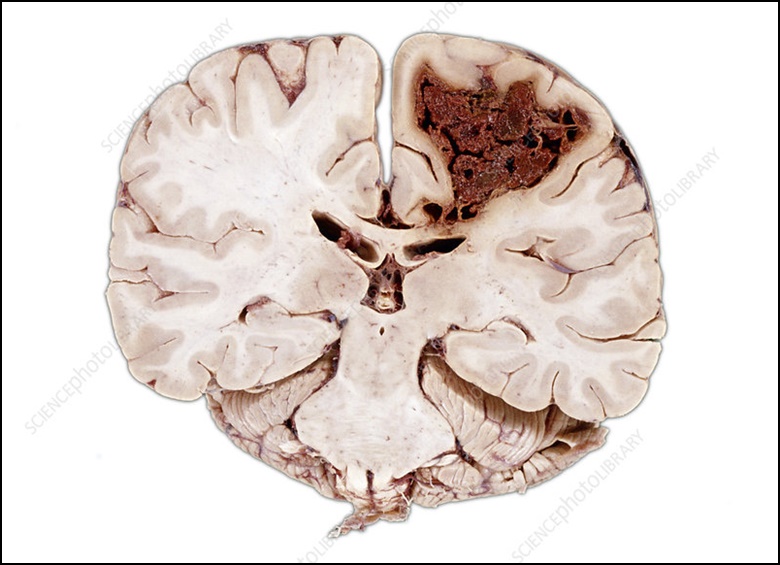

골든타임을 놓쳐 뇌세포 괴사가 시작된 경우 뇌경색 치료는 혈관을 뚫게 되는데 혈관을 다시 뚫는다고 해도 후유증이 심각하게 남거나 악화될 수 있으며 심한 경우 사망에 이르는 경우도 적지 않습니다.

ct 및 mri 검사를 받아 뇌경색 증상이나 출혈 유무를 확인합니다. 뇌경색 증상은 여러 종류이기에 어느 종류의 뇌경색인지를 파악하거나 머리 혈관의 모양을 입체 영상화하는 mra 검사를 받기도 합니다. 이런한 검사를 통해 뇌 동맥 경화가 진행되어 가늘어진 혈관 및 동맥류를 확인하게 됩니다.